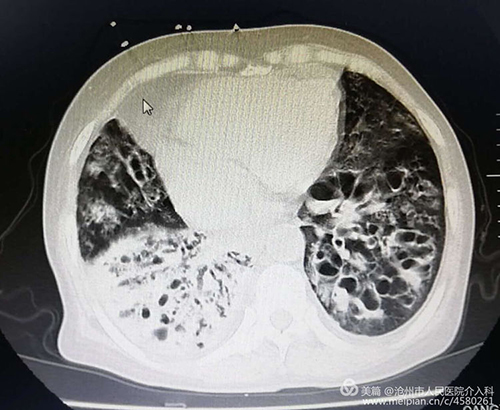

患者女性,67岁,大咯血,重度支气管扩张并感染、肺结核、肺气肿病史30余年,并肺动脉高压、肺心病、右心衰。曾于县、市多家医院及北京协和医院多次治疗心肺功能极差,外院应用止血药物无效,转入我科。下图为术前CT急诊行介入治疗,术中造影可见双侧支气管动脉均异常粗大,是出血的罪犯血管。栓塞后患者咯血即停止,效果立竿见影。